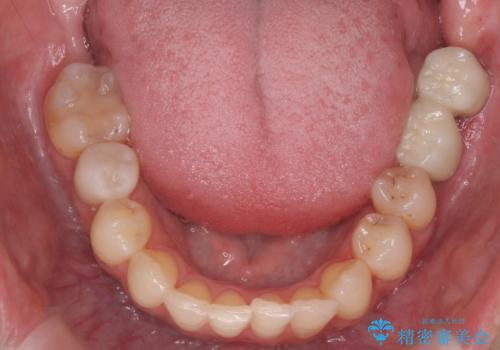

あきらめないで!!虫歯でボロボロでも大丈夫! 非抜歯矯正と虫歯、インプラント治療で見違える歯並びに。

虫歯が多数、また奥歯も欠損してしまっていました。

左下の親知らず、左上の小臼歯が残根状態で一本抜いたほかは抜かずに矯正しました。